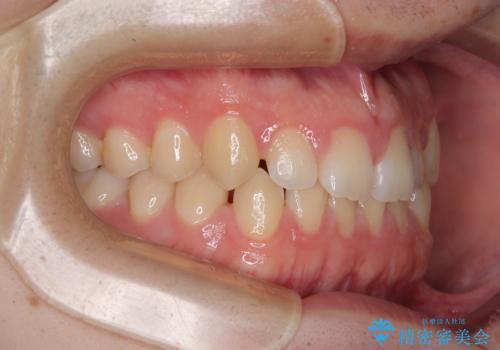

- 「前歯のすきっ歯が気になる」「食べ物が歯の間に詰まりやすい」とのお悩みで来院された20代男性の患者様です。

歯と歯の間に隙間がある**空隙歯列(すきっ歯)**は、見た目の問題だけでなく、食片圧入による歯肉の腫れや、隣接面う蝕のリスク増加につながることがあります。

診査により舌突出癖が認められました。この癖は、すきっ歯の原因となるだけでなく、矯正後の後戻りリスクを高めます。